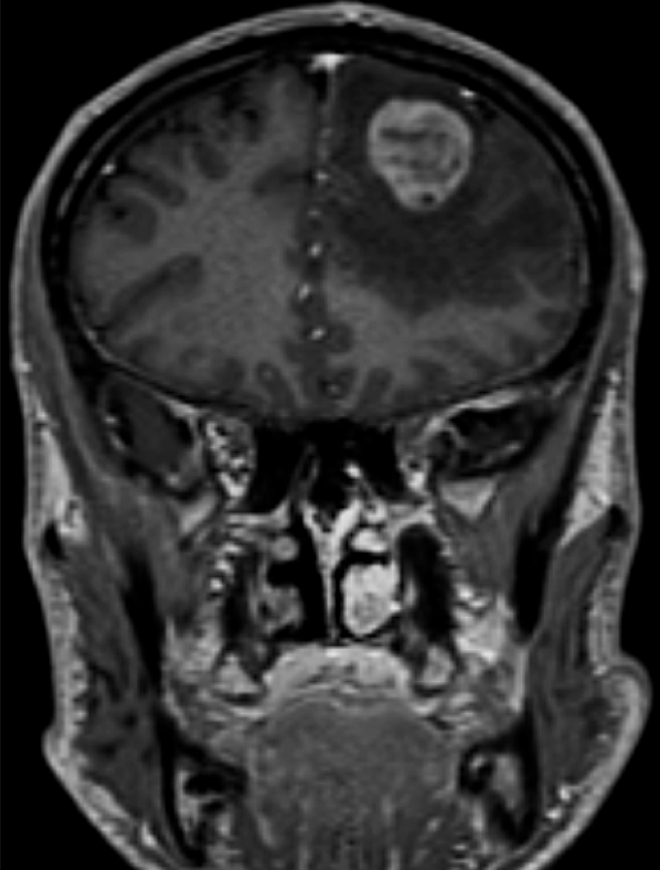

L’association d’une hyper-réflexivité ostéo-tendineuse de l’hémicorps droit avec signes de Hoffmann et de Babinski droits signifie qu’il existe une atteinte de la voie pyramidale droite. Comme le syndrome pyramidal est associé à des troubles de la parole, il faut d’emblée évoquer une origine encéphalique et non pas médullaire. Puisque le syndrome pyramidal est hémicorporel droit, on recherchera une atteinte encéphalique controlatérale, de l’hémisphère gauche, qui explique bien l’association à des troubles de la parole.